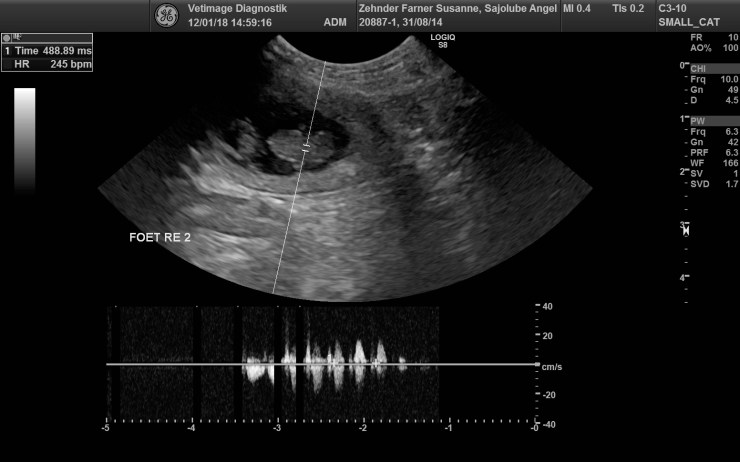

17. Januar 201818. Januar 2018BenjaminHinterlasse einen Kommentar auf Ultraschall Angel Ultraschall Angel Wir erwarten vier Welpen von unserer Malteser Hündin Angel auf Mitte Februar. Ultraschall Angel Teilen mit: Auf X teilen (Wird in neuem Fenster geöffnet) X Auf Facebook teilen (Wird in neuem Fenster geöffnet) Facebook Gefällt mir Wird geladen … Ähnliche Beiträge